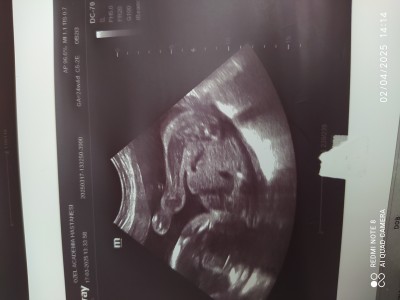

2 Nisan Doğum kategorisinde (127 puan) sordu

Kızlar lütfen tahminınızı ögrenebılırmıyım

Gebelik haftası 27

Doktorumda kız dedı hepınıze cok tesekkur ediyorum bakalım Dogsun hayırlısıyla ıkı oğlum var bunada kız dedı dualarda buluşalım kardeslerım